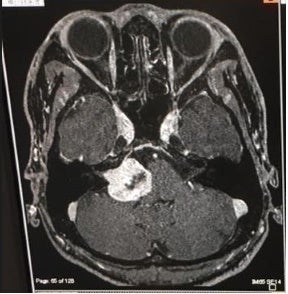

ところが、23歳の若さで自分が

脳腫瘍に侵されていると判明し

25歳のとき、脳腫瘍摘出手術を行いました。

誰が見てもわかる脳腫瘍がありました

腫瘍の97%は摘出でき、手術は成功。